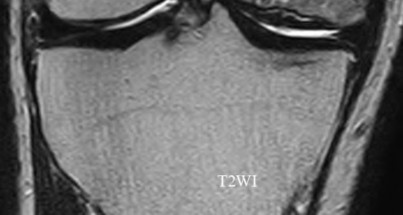

Question 7

A 65-year-old man presents with progressive clumsiness in his hands, difficulty buttoning his shirt, and a broad-based gait. A T2-weighted MRI shows spinal cord compression with intrinsic cord signal change at C4-C5.

Which of the following MRI findings is associated with the poorest prognosis for neurological recovery after surgical decompression in cervical spondylotic myelopathy?

Explanation

In cervical spondylotic myelopathy, the presence of T1 hypointensity corresponding to a T2 hyperintense lesion indicates myelomalacia or cystic necrosis of the spinal cord. This finding is a strong predictor of poor functional recovery following surgical decompression.